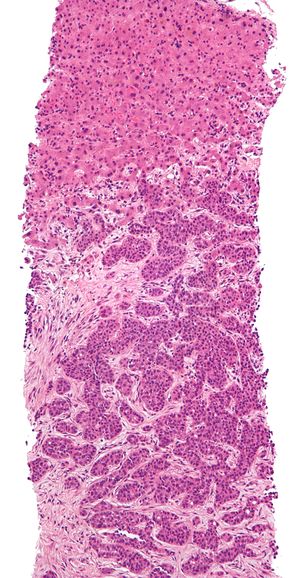

الخزعة biopsy تطلق على الجزيء المنتزع من الجسم الحي لدراسته نسجياً بغية تحديد مدى وطبيعة التبدلات المرضية فيه للمساعدة على وضع تشخيص الحالة المرضية وتدبيرها بالتالي.

يمكن تصنيف هذه الأنواع بحسب الغاية التي تجرى لها الخزعة أو بحسب طريقة إجرائها. فمنها ما يؤخذ جراحياً بغية التشخيص النسيجي، وتكون إما جزئية وإما استئصالية excisional حيث تشمل استئصال العضو المصاب بكامله ودراسته نسيجياً. ومنها ما يؤخذ عن طريق إبرة خاصة تغرس في العضو المصاب لأخذ جزيئة منه ودراستها، ويتم ذلك إما مباشرة أو بعد تصويب الإبرة نحو الآفة المشبوهة بتصويرها بالأمواج فوق الصوتية أو بالتصوير الطبقي المحوري، وتسمى هذه الخزعة بالإبرة الموجهة، وكمثال على ذلك تجرى هذه الخزع في سرطانات الموثة وآفات الثدي.